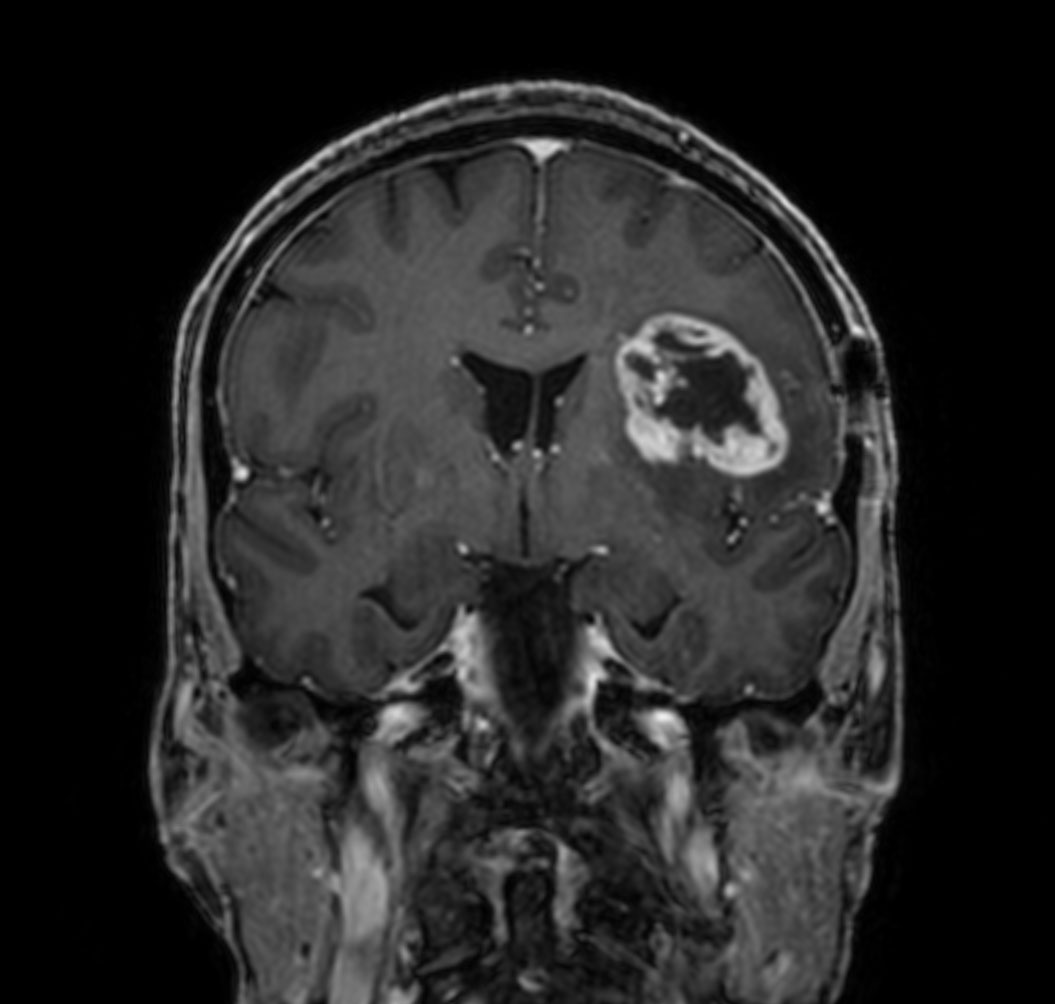

T1w 3D TFE

-